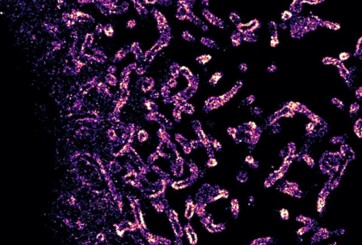

Komplexe Zuckerstrukturen auf der Zelloberfläche

… sollen Aufschluss über die Entstehung von Krebs geben. Die Glycocalyx ist eine hochkomplexe Struktur aus Zuckern, die jede Zelle im Körper umgibt. Wie die molekulare Organisation der Glycocalyx aussieht, wie sie durch genetische Veränderungen beeinflusst wird und wie diese auf zelluläre Prozesse rückkoppeln, ist Gegenstand der Forschung von Leonhard Möckl, Leiter der Forschungsgruppe ›Physikalische Glycowissenschaften‹ am Max-Planck-Institut für die Physik des Lichts in Erlangen. Für seine Forschungsvorhaben erhielt der Wissenschaftler gleich drei Grants in Höhe von insgesamt circa 580.000…